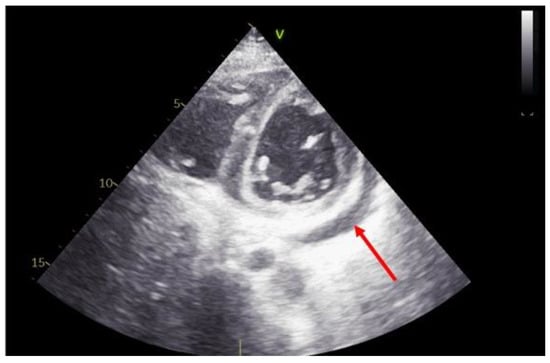

2.4. Valve Morphology and Function